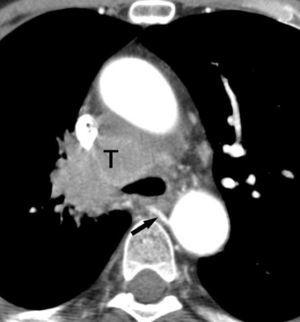

Valoración del tumor

El estadio tumoral (T) se basa en el tamaño, localización y relación con las estructuras adyacentes valorado mediante TC. Los tumores T1 son aquellos de 3 cm o menores en su diámetro mayor, rodeados de pulmón y que no invaden la pleura visceral ni los bronquios principales, mientras que los T2 son lesiones mayores de 3 cm, o aquellas que invaden la pleura visceral o al bronquio principal a más de 2 cm de la carina o que condicionan atelectasia o neumonitis obstructiva que no afecte a todo el pulmón. La diferenciación entre ambos estadios tumorales suele ser sencilla mediante TC, salvo la afectación de la pleura visceral, aunque esta no tiene un impacto importante en el manejo clínico. El tumor T3 viene determinado por la infiltración de estructuras vecinas potencialmente resecables, como la pared torácica, diafragma, pleura mediastínica, pericardio parietal o si el tumor está situado a menos de 2 cm de la carina (fig. 1). Los tumores T4 son aquellos que no pueden ser resecados porque engloban a estructuras vitales, invaden el corazón, grandes vasos, esófago o cuerpos vertebrales (fig. 2) o en los que existe un nódulo o nódulos en el mismo lóbulo del tumor. Además de definir la T, es importante reflejar las particularidades de la infiltración de estructuras en vecindad que puedan modificar la actitud terapéutica. Por ejemplo, cambiará la estrategia quirúrgica según el tipo de bronquio afecto o la estructura mediastínica infiltrada, si es sólo la grasa, o un vaso; cuando existe neumonitis o atelectasia secundaria a un tumor central, la planificación del campo de radioterapia dependerá del límite entre la masa y la repercusión pulmonar.

La diferenciación entre tumores T3 y T4 puede ser difícil empleando sólo técnicas de imagen. Cuando se evidencia destrucción ósea (costal o vertebral), existe masa en el espacio intercostal (fig. 3), o las estructuras mediastínicas están claramente englobadas por el tumor, el diagnóstico es obvio (fig. 2). Sin embargo, sin estos hallazgos, la predicción de invasión es mucho menos fiable. Se han descrito diferentes signos que pueden ayudar a determinar la invasión de pared torácica. Éstos incluyen el contacto con la superficie pleural mayor de 3 cm, el engrosamiento pleural, la ausencia de plano graso y la presencia de un ángulo obtuso entre el tumor y la pared torácica. Aplicando al menos dos de estos criterios la sensibilidad es de un 87%, sin embargo la especificidad es baja (59%)4. El dolor torácico localizado es un síntoma importante que a menudo está asociado a invasión de pared.

Fig. 2.--T4. (A) Corte axial de tomografía computarizada (TC) torácica con contraste. Tumor hiliar derecho que infiltra la arteria pulmonar derecha, la vena cava superior y engloba al bronquio intermediario. (B) Reconstrucción coronal oblicua, longitudinal al eje de la arteria pulmonar derecha, que muestra cómo engloba el tumor a la rama del truncus superior (flecha blanca) e inferior (flecha negra).